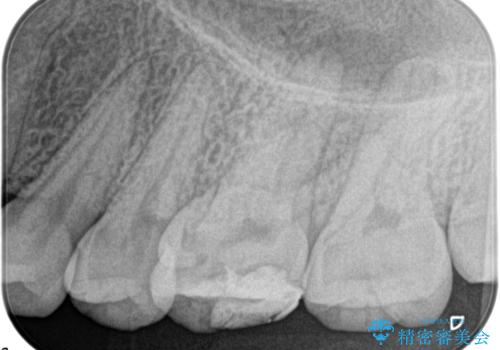

奥歯の根管治療

- 定期検診にて根尖に病変を認めた患者様です。

歯髄壊死の診断にて根管治療を行っております。